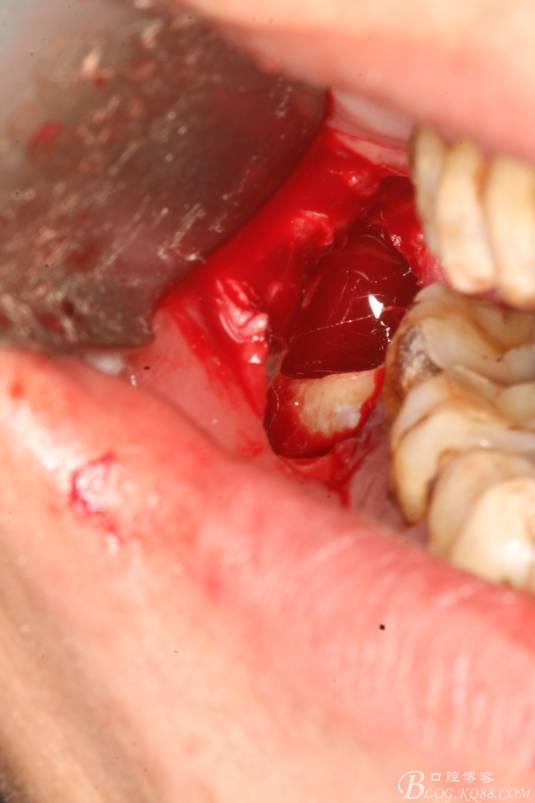

2.切開(kāi)翻瓣

3.去骨、暴露48.

4. 縱分牙根和牙冠